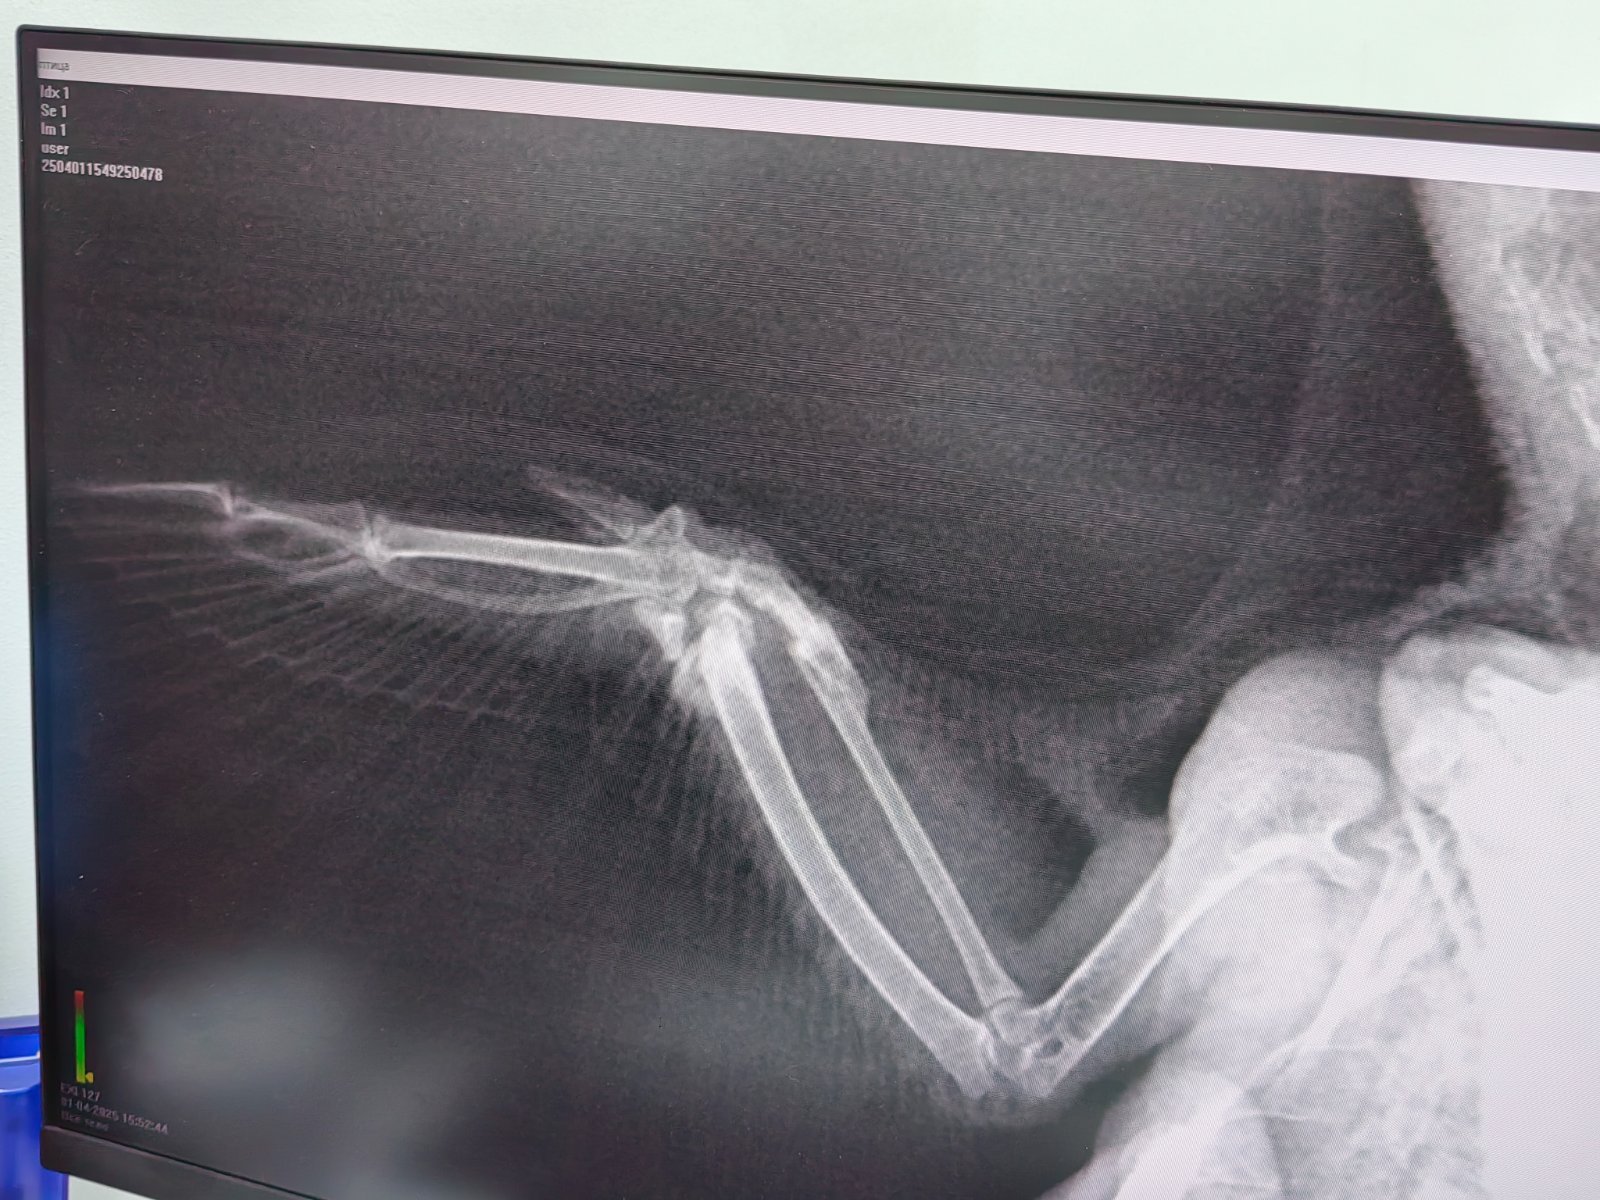

Бусенка Опубликовано 1 апреля, 2025 Автор #17 Опубликовано 1 апреля, 2025 В 25.03.2025 в 14:49, маленький принц сказал: если кроме крыла переломов нет а плечевой сустав целый то достаточно проекцию лёжа не спине ВНИМАНИЕ за три часа до рентгена НЕ поить и НЕ кормить чтобы не мог захлебнуться содержимым зоба при манипуляциях Здраствуйте! Сделала рентген, файл прикреплен. Скажите пожалуйста, что видно? И нужно ли что-то добавить по лечению? Спасибо! 2

Zosia Опубликовано 4 апреля, 2025 #22 Опубликовано 4 апреля, 2025 Перелом, там и лучевая, и локтевая, и сам сустав поврежден. Но уже хорошая консолидация отломков. Остеогенон и артрогликан пить, причем Остео- достаточно 21 день (т.к. консолидация уже идет), а вот артрогликан- 40 дней. 3

Бусенка Опубликовано 15 мая, 2025 Автор #42 Опубликовано 15 мая, 2025 @Zosia Добрый день! для инфо. дублирую повторный снимок после 40 дней лечения. ответ по воцап получен. продлить лечение - давать остеогенон 2